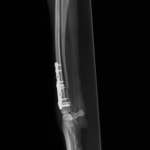

症例3:キルシュナーワイヤーのピンニングによる整復

ペルシャ猫 11ヶ月齢 雄

他院にて左大腿骨遠位の成長板骨折(salter-harrisⅠ型)が認められており、治療相談を目的として来院。当院にて、キルシュナーワイヤーを用いたピンニングにより骨折部位の整復を行いました。術後の経過は良好で、現在も経過観察中です。

術前レントゲン

術後レントゲン

Arthrex社のターゲティングデバイスを用いてピンニングの位置を調整することで、確実な固定を行っています。当院ではこの手術器具以外にも、人の手術にも使用される様々な器具を導入し、手術精度を高め、また医療メーカーと新しい器具の開発、試作にも取り組んでおります。